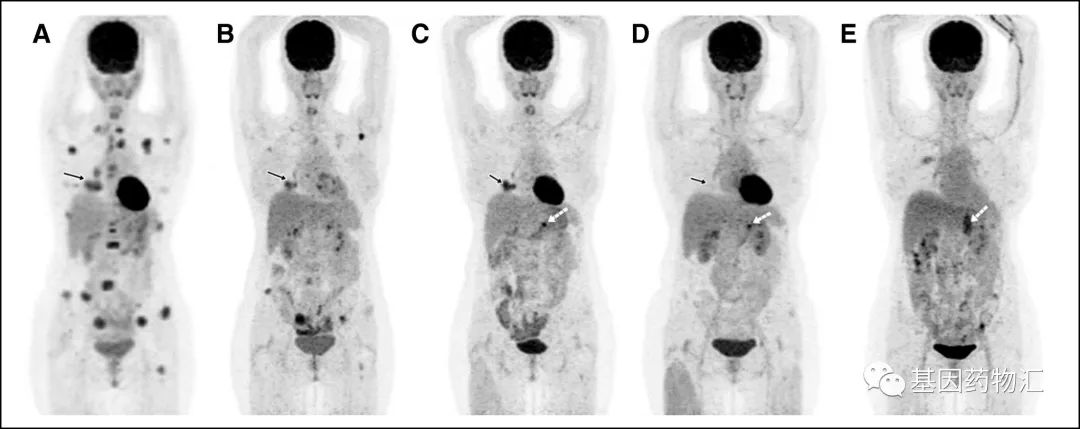

我们曾经讲过这样一个经典的案例。这名患者是一位74岁的老太太,毕生从未吸烟,在一次检查中发现血液癌胚抗原水平升高,因此接受了胸部CT检测,并最终确诊为T4N1M1c,即ⅣB期肺腺癌。

患者的胸部CT扫描图像,肺部巨大的阴影以及周围的小结节非常惊人。

除了肺部的病灶,患者颅内的转移病灶也数量惊人,根据增强MRI的检查结果,病灶总共超过20个!属于非常典型的多发脑转移。

高龄、晚期、多发转移,这样的患者还有希望通过药物治疗达到缓解吗?事实上,在接受了仅仅5周的奥希替尼治疗之后,患者颅内的病灶,竟然完全消失了!

对于部分患者,尤其是将奥希替尼作为一线治疗方案的患者,脑部放疗完全可以推迟,甚至部分响应良好的患者根本不需要脑部放疗。

这说明,在某些特殊的情况下(比如患者可能很难耐受放疗,或颅内转移病灶数量过多等),可以考虑先使用奥希替尼治疗。如果患者对于药物的响应良好,很可能奥希替尼的治疗能够为脑部放疗提供条件,或者直接凭借药物治疗完全消除病灶。

从脑转移的缓解率上来说,FLAURA试验证实了,奥希替尼治疗脑转移病灶的控制率比厄洛替尼和吉非替尼更高,穿过血脑屏障的能力更强。